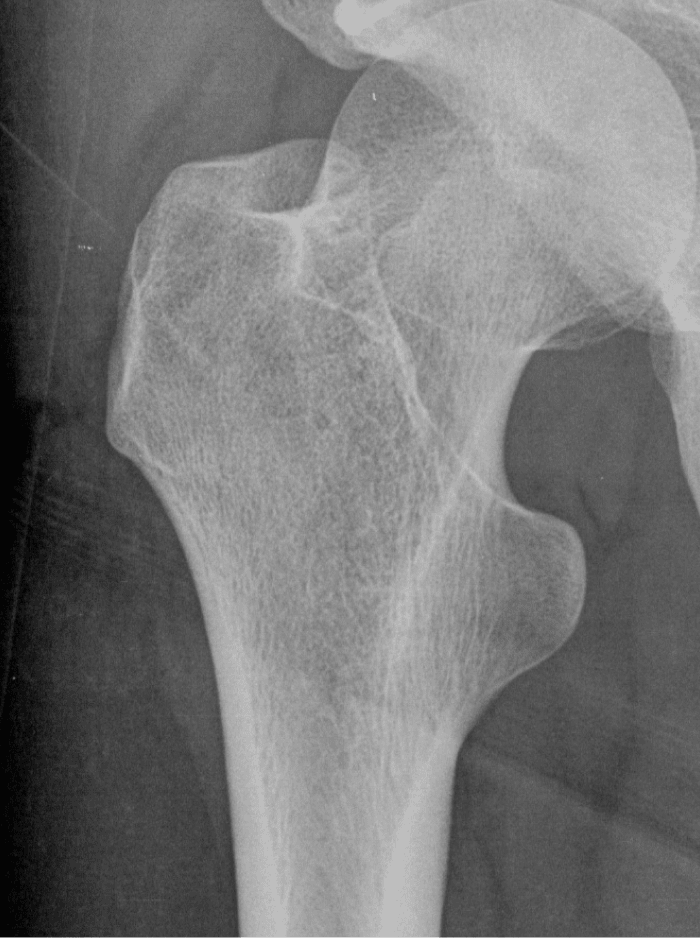

X-ray of right hip osteoporosis, age 54

DEXA result summary of right hip, age 65

DEXA result summary of right hip, age 54

DEXA result summary of lumbar spine, age 65

DEXA result summary of lumbar spine, age 54